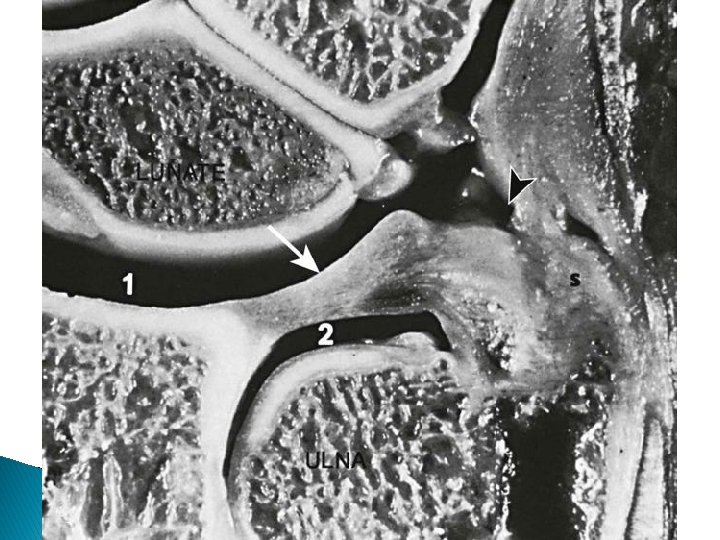

Articulations and Ligamentous Support � Distal radioulnar joint ◦ Supination and pronation � Radiocarpal joint ◦ Flexion and extension ◦ Radial and ulnar deviation �Radial collateral ligament � Triangular fibrocarilaginous complex (TFCC) ◦ On the ulnar side �Composed of an articular disk, ligaments and bone �Dissipates stresses on forearm during loading �Damaged by forced extension and pronation

� http: //www. imageinterpretation. co. uk/wrist. h tml